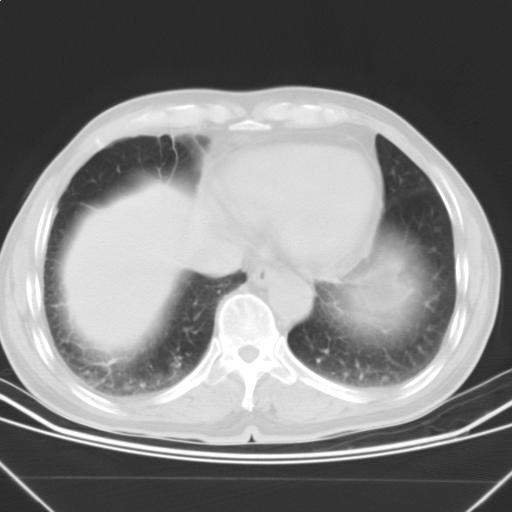

以下是引用随光逐影在2009-5-1 13:53:00的发言:[br]考虑为:1)两肺血行播散型肺结核;2)右肺下叶炎症感染。3)右侧胸膜增厚。